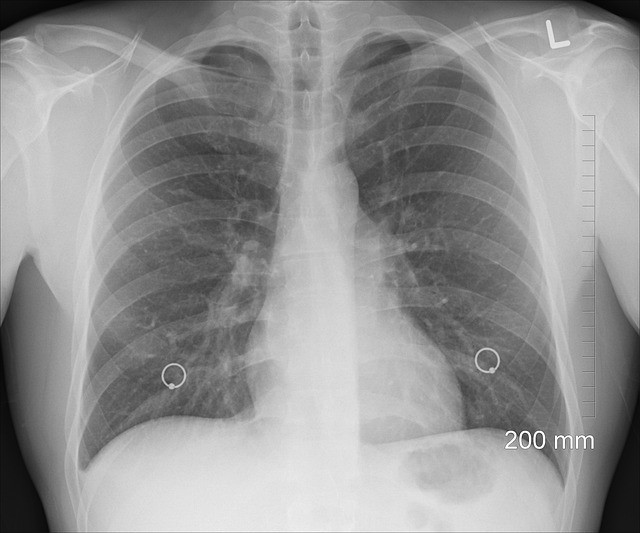

늑간신경통은 갈비뼈 사이를 지나는 신경에 염증이나 압박이 생겨 발생하는 통증성 질환입니다. 날카롭고 쑤시는 통증이 가슴이나 옆구리, 등 쪽에서 발생하며, 깊게 숨을 들이쉴 때나 기침, 재채기할 때 통증이 심해지는 것이 특징입니다. 이 통증은 때로는 심장 질환이나 위장 질환으로 오해될 만큼 유사하게 나타나기 때문에 올바른 진단이 중요합니다. 이번 글에서는 늑간신경통의 다양한 원인, 구체적인 증상, 그리고 효과적인 치료법까지 하나씩 자세히 살펴보겠습니다.